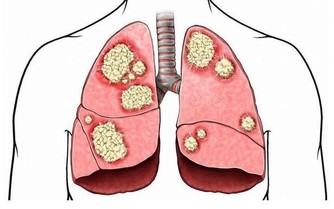

因為蝦體內多有肺吸蟲的囊蚴和副溶血性弧菌等,